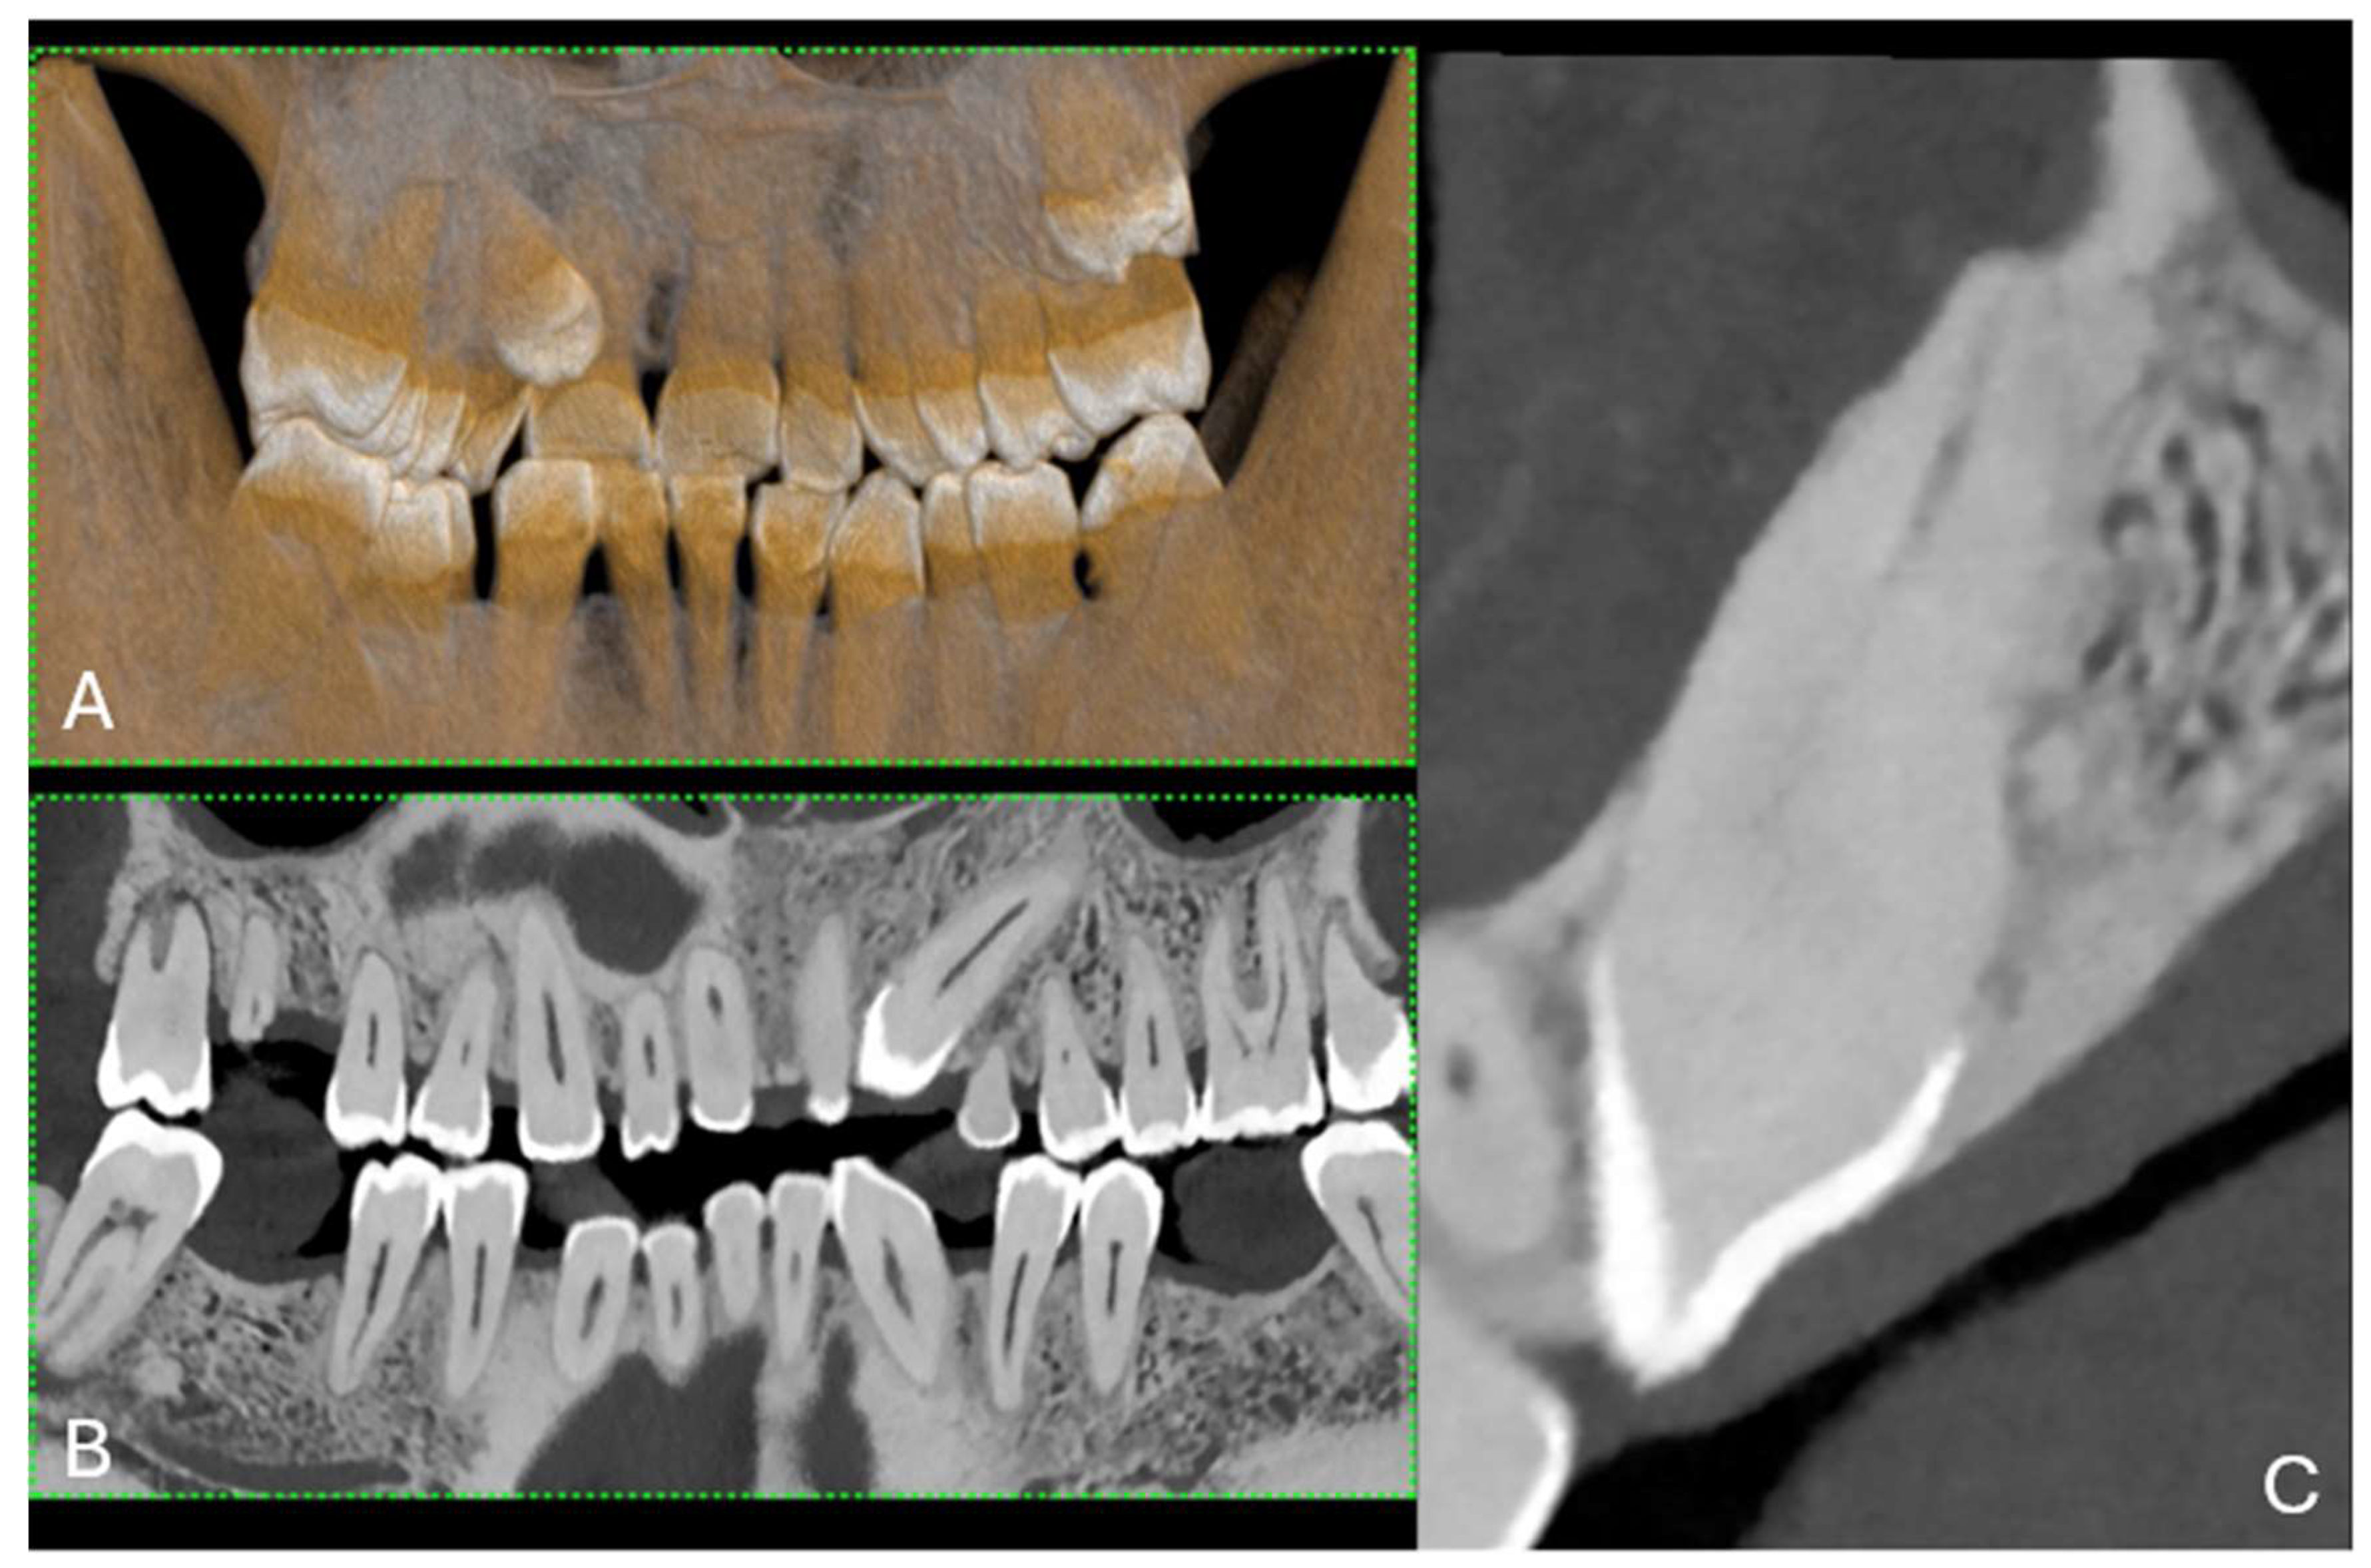

Three-dimensional (3D) image reconstructions using the volume rendering technique (VRT) are helpful for advanced analysis in clinical settings, for enhancing visualization and interpretation, and for understanding complex anatomical and dental structures. They are beneficial for diagnosis, the treatment planning of maxillofacial lesions, educational demonstrations, and teaching in medical training [17] (Figure 4 and Figure 5).

Figure 4. (A) A 3D cinematic rendering that displays the detailed structure of a jaw with teeth, emphasizing their three-dimensional form and alignment. (B) The longitudinal MPR showing the teeth, fillings, and jawbone with high contrast, which is useful for evaluating dental health and anatomy. The scan was performed on a commercial whole-body Dual Source Photon Counting CT scanner (NAEOTOM Alpha, Siemens Healthineers); 0.2 mm slice thickness, 0.1 mm reconstruction increment, FOV 140 mm, spiral acquisition with tube current modulation; resolution matrix of 1024 × 1024 pixels on the source axial reconstructions with a kernel filtering of Bv72; maximum intensity of Quantum Iterative Reconstruction (QIR 4). The actual displayed resolution is 0.1 mm (100 microns). Abbreviations: 3D, three-dimensional; MPR, multiplanar reconstruction; FOV, field-of-view.